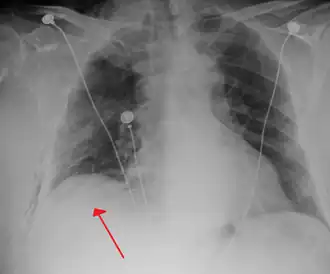

-

Anteroposterior inspired X-ray, showing subtle left-sided pneumothorax caused by port insertion -

Lateral inspired X-ray at the same time, more clearly showing the pneumothorax posteriorly in this case -

Anteroposterior expired X-ray at the same time, more clearly showing the pneumothorax in this case -

Chest X-ray showing a pneumothorax on the right (left in the image), where the absence of lung markings indicates that there is free air inside the chest -

Chest X-ray showing the features of pneumothorax on the left side of the person (right in image)